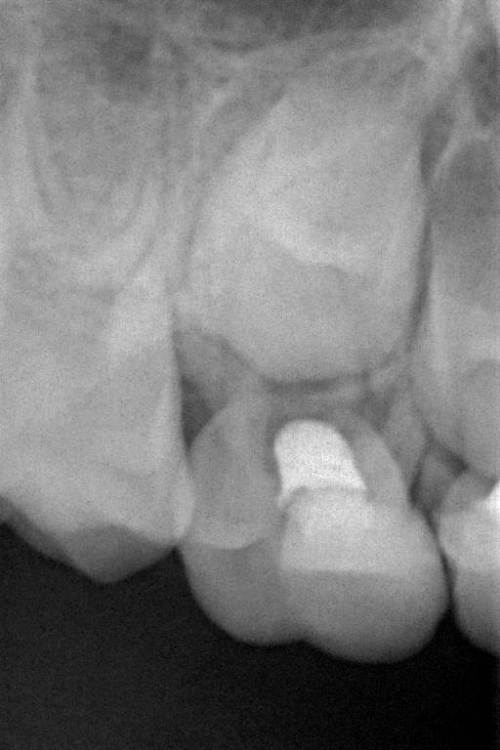

Свищ на десне у 5ки -молочный

добрый день. У ребенка 7 лет образовался свищ у молочной 5ки. зуб не беспокоит, зуб 2 года назад лечили, пульпит.

Можно ещё сохранить зуб? Если да, то как должно проходить лечение?